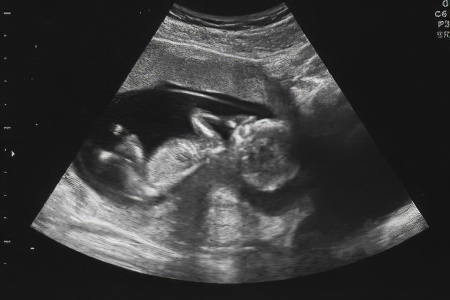

УЗИ, проведенное на сроке 20-24 недели, позволяет оценить следующие аспекты течения беременности:

- Точный срок гестации;

- Соответствие размеров плода сроку беременности;

- Возможные аномалии развития (например, порок сердца);

- Объем околоплодных вод;

- Состояние плаценты, миометрия матки и риск предлежания;

- Пол будущего ребенка.